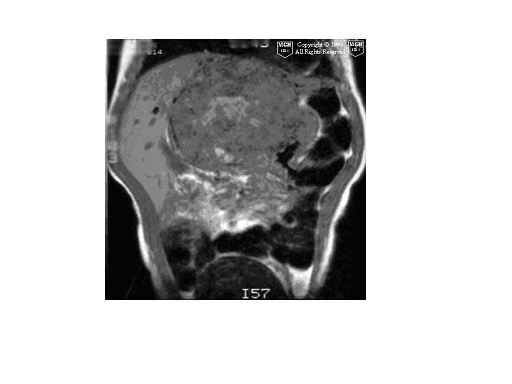

患者男性,10岁,腹痛4小时余,5年前患乙肝.查:右上腹压痛(+),反跳痛(+)血常规:wbs13.5x10(9)/l,b超提示:右肝实质性占位,性质待查.afp弱阳性患者男性,10岁,腹痛4小时余,5年前患乙肝.查:右上腹压痛(+),反跳痛(+)血常规:wbs13.5x10(9)/l,b超提示:右肝实质性占位,性质待查.afp弱阳性.

肝右叶巨大类圆形混杂密度影,边缘清晰,病变内部密度不均匀,可见环形钙化,我们考虑肝脏恶性肿瘤,肝母细胞瘤或肝细胞癌.请大家就平扫给予分析和指教.谢谢!!患者直接上省级医院检查,未做增强!

肝影增大,肝右叶巨大类圆形混杂密度影,边缘清晰,病变内部密度不均匀,可见环形钙化,我们考虑肝脏恶性肿瘤,肝母细胞瘤可能性大,有乙肝病史肝细胞癌不完全除外。!

肝右叶见团块状混杂密度影,体积较大,密度不均匀,其内见低密度坏死区,并见点状、条状高密度钙化影,患者10岁,上腹痛,afp弱阳性,5年前患乙肝,首先考虑肝细胞癌,纤维板层样肝细胞癌不除外。增强扫描可鉴别,纤维板层样肝细胞癌,临床无特异性,以腹块和上腹部不适为主,无病毒性肝炎病史,实验室检查hbsag 阴性afp正常或略升高,ct表现病灶内出现钙化为其特点。

肝右叶巨大类圆形混杂密度影,边缘清晰,病变内部密度不均匀,可见环形钙化,结合临床考虑肝母细胞瘤可能性大。